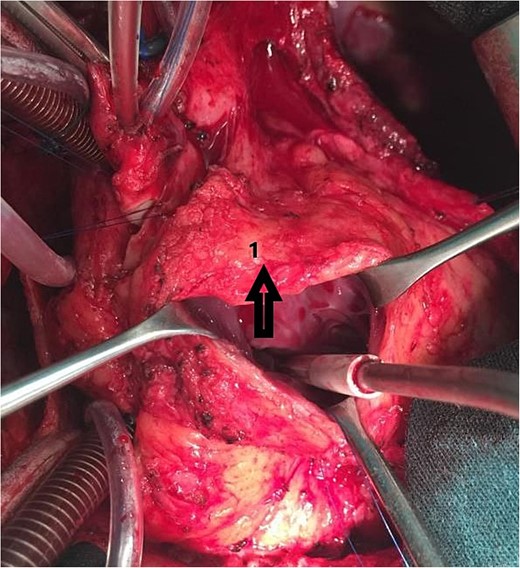

An 11-year-old girl was referred to our hospital with a main complaint of progressive exertional dyspnea. She had undergone surgical repair of SAS 6 years ago. Transthoracic echocardiogram (TTE) revealed the following findings: severe left ventricular hypertrophy, tunnel-like fibromembranous subaortic stenosis with a length of 10 mm, a peak gradient (PG) across the LVOT of 170 mmHg, and mild aortic regurgitation. Based on these findings, the patient was scheduled for elective surgical repair with a possible indication for MKO. The operation was performed via median sternotomy with great caution to avoid inadvertent rupture of any cardiac cavity due to heavy adhesions from the previous operation. The aorta was cannulated just below the takeoff of the innominate artery. Bicaval cannulation was performed to provide a bloodless field. Aortic cross-clamping was applied, and antegrade cold blood cardioplegic solution was administered via a catheter placed in the ascending aorta. The ascending aorta was opened transversely 1 cm above the sinotubular junction (Fig. 1). The aortic valve leaflets were examined carefully to confirm that the aortic valve could be preserved. LVOT was examined thoroughly, and it was clear that the stenosis in the subaortic area was so complex that simple resection through the aortic valve orifice would not be sufficient. The right ventricular outflow tract was opened transversely below the pulmonary valve. The conal papillary muscle was identified (Fig. 2). A right-angle instrument was introduced through the aortic orifice into the interventricular septum, and the tip of the instrument was used to perforate the conal septum to the left of the conal papillary muscle to prevent damage to the conduction system; the septal incision was completed with great caution to avoid damage to the aortic cusps and to extend the incision downward as necessary to completely relieve the stenotic subaortic area (Fig. 3). Interrupted 5/0 Prolene sutures were placed circumferentially around the septal incision to close the interventricular septal defect using a bovine pericardial patch to provide adequate widening of LVOT (Fig. 4). The right ventriculotomy was closed with a second bovine pericardial patch to avoid any possible obstruction of the right ventricular outflow tract (Fig. 5). The remainder of the operation was completed uneventfully. After 6 hours of mechanical ventilation, the patient was extubated, and she convalesced well postoperatively. TTE showed excellent results of the operation with PG across LVOT of 20 mmHg. On 1 year follow-up, the patient was asymptomatic and in very good general condition, and TTE findings confirmed the excellent result.

Intraoperative image showing the interrupted sutures placed around the septal incision.